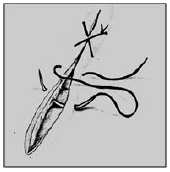

Nas suturas interrompidas os fios são fixados separadamente, podendo variar a tensão de acordo com a necessidade em cada ponto. É considerada mais segura, já que o rompimento de um ponto não inviabiliza a sutura toda. É menos isquemiante, confere maior permeabilidade à ferida e consegue força tensil maior e de modo mais rápido. Como desvantagens, possui uma elaboração mais lenta e trabalhosa. Relacione os tipos de sutura com as imagens e assinale a alternativa que apresenta a ordem correta.

1. Sutura em Jaquetão.

2. Sutura em “X” ou Sultan.

3. Sutura de Mayo.

4. Sutura de Halsted.